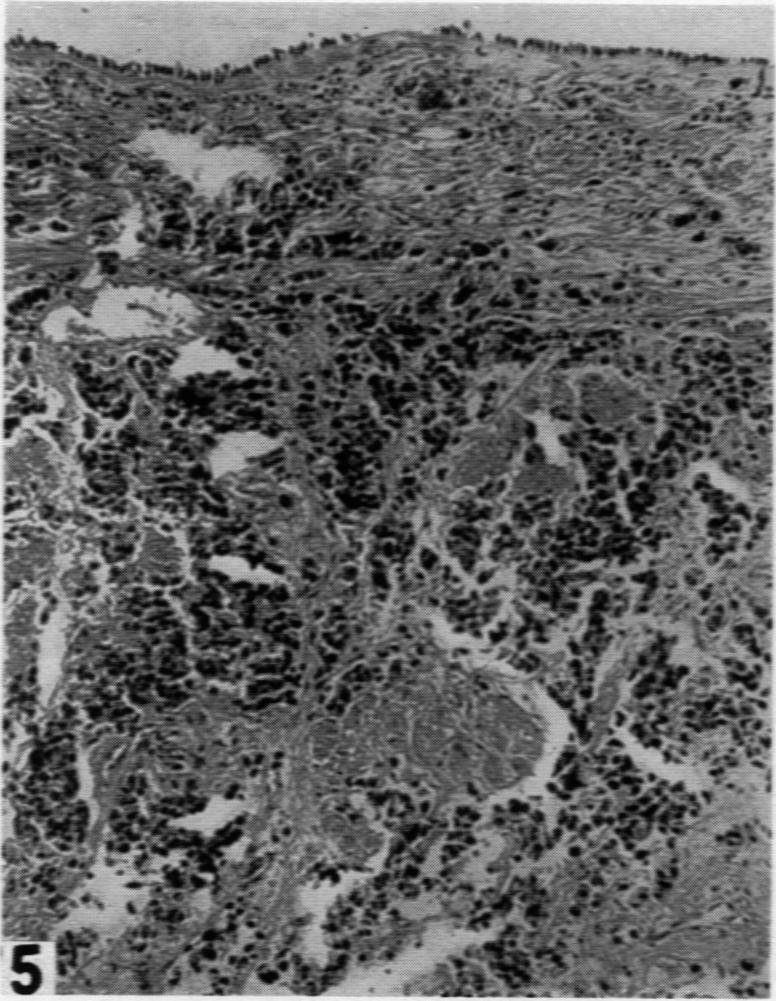

Bronchiogenic Carcinoma in Association with Pulmonary Asbestosis: Report of Two Cases.

Am J Pathol. 1942 Jan;18(1):123-35.